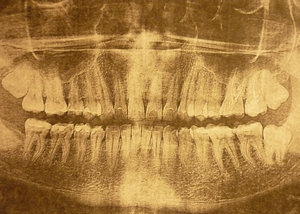

У меня два нижних зуба мудрости выросли неправильно, т.е. горизонтально, вылезли не полностью, а частично торчат. Один уже с кариесом и даже откололся.

Стоит ли удалить два нижних ретенированных зуба мудрости одновременно?